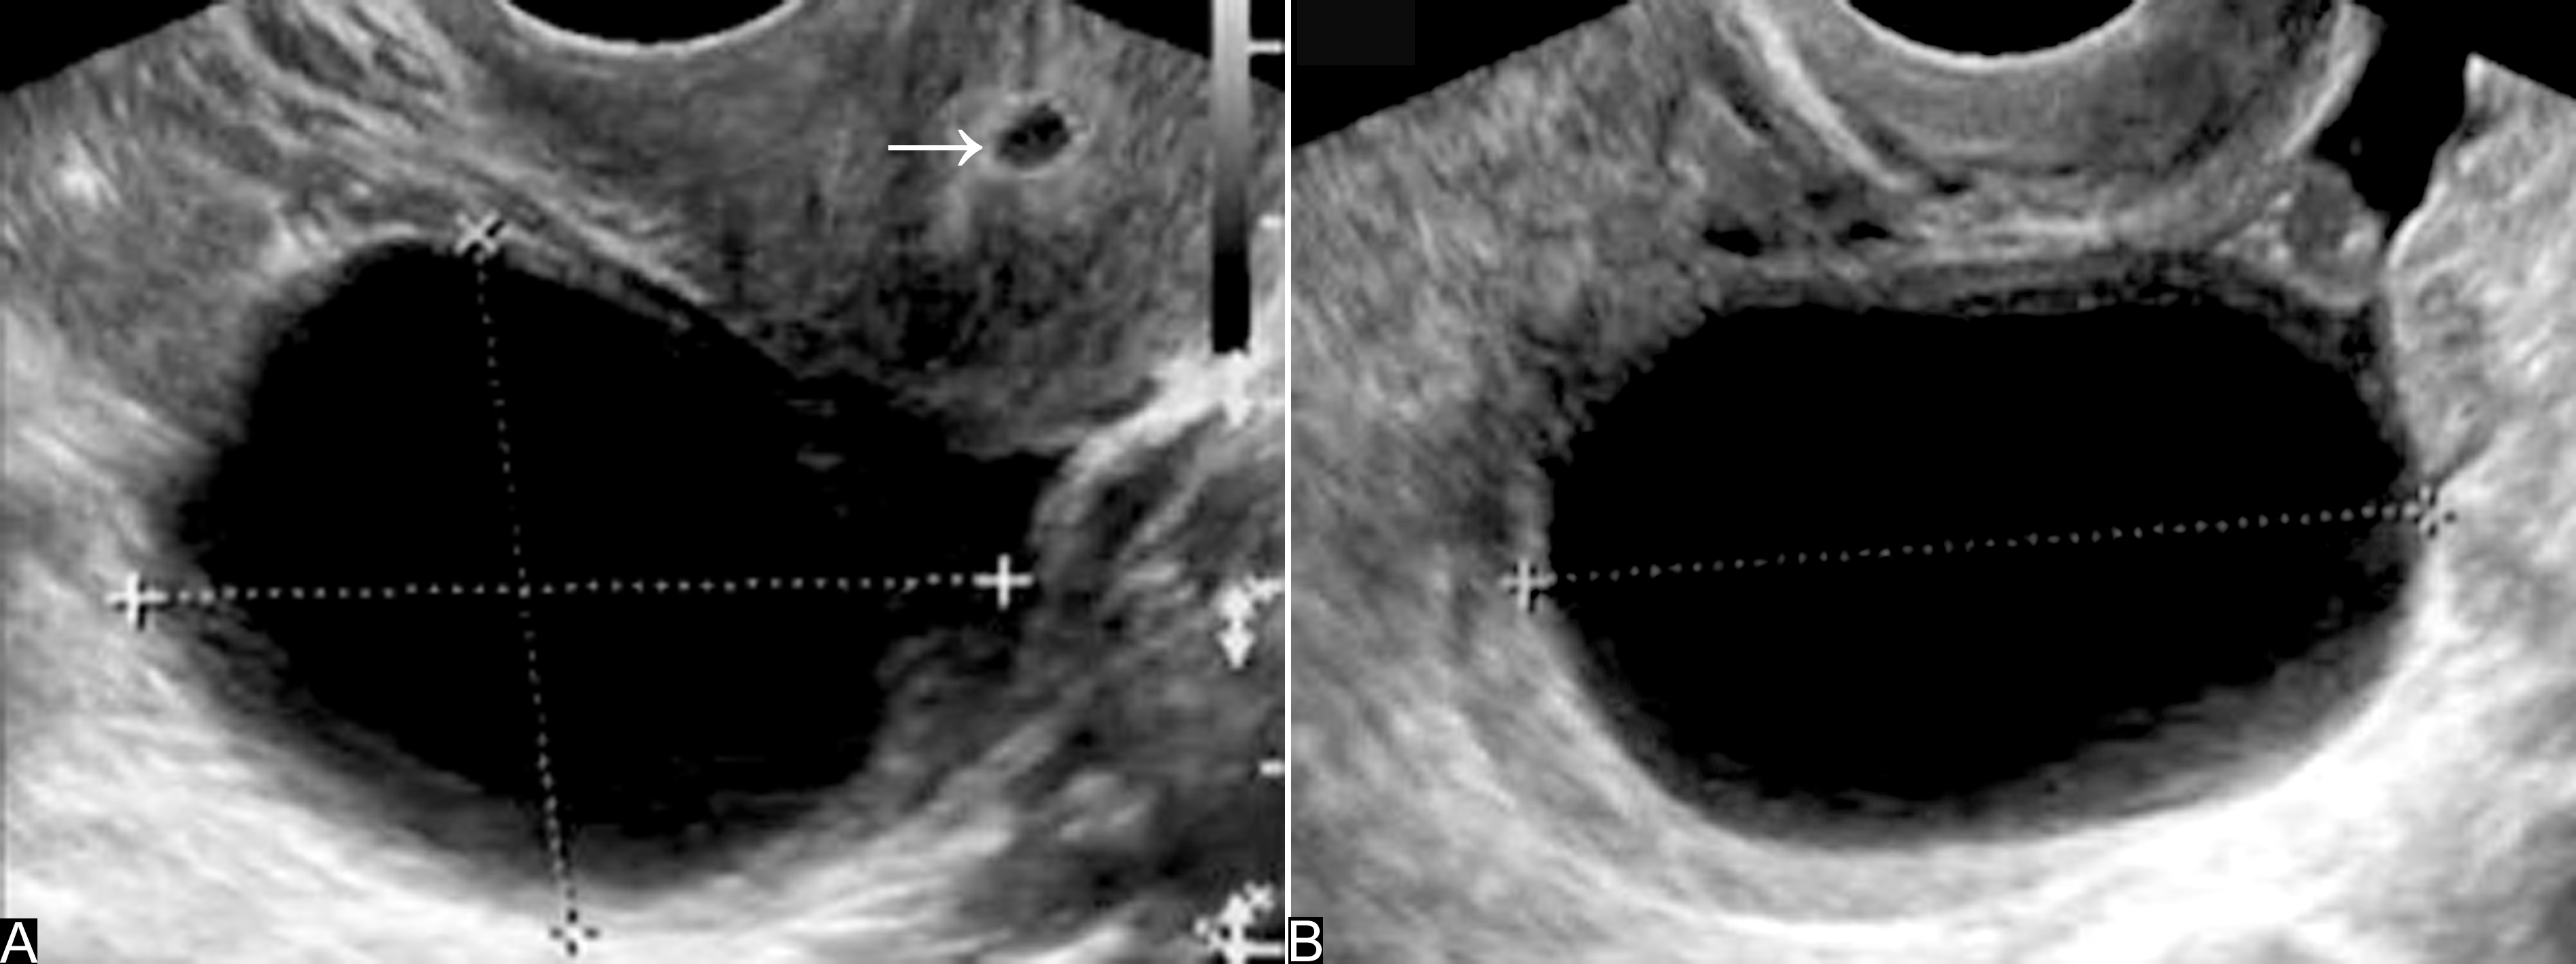

检查时要注意囊肿的壁有无乳头状突出物或内部有无实性回声区的存在。

一般认为,内部的这些回声常提示为乳头状肿瘤,应当注意有恶性的可能(图5,6),临床常采取积极的态度进行处理。

图5卵巢恶性粘液瘤声像图

A、B:宫旁瘤体显示瘤体回声,形态不规则,边缘不清楚;囊壁厚薄不一